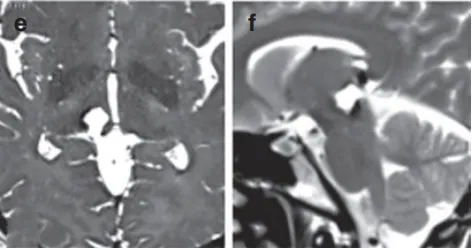

最终,把教授通过幕下小脑上入路,巧妙避开重要血管,为Anne完整切除了血管瘤。术后MRI清晰显示病灶消失,她不仅没出现新的神经功能缺损,并在术后第10天就顺利出院!

术后MRI影像